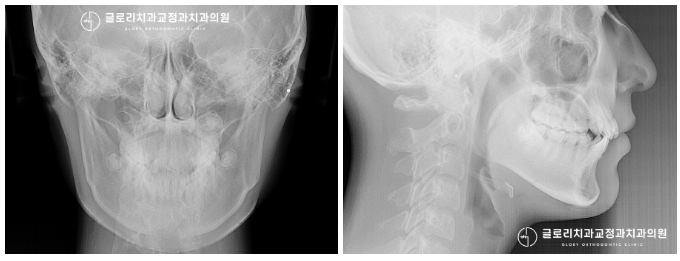

세팔로 사진에서 볼 수 있듯이

악관절에도 문제가 없는 것으로 확인이 되었습니다.

다행히, 좌우대칭도 정상 범위에 속해있네요^^